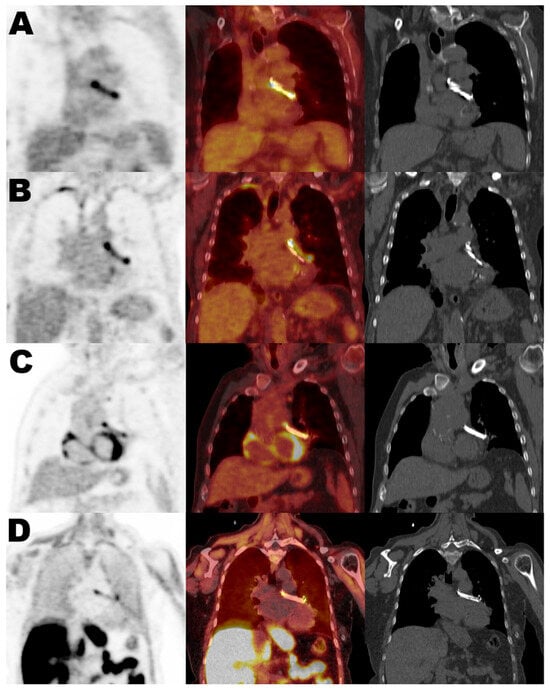

False-Positive PET Uptake in Left Atrial Appendage Closure Devices Due to Postoperative Inflammatory Response

by Marta Hernández-Meneses, Guillermo Cuervo, Marta Tormo-Ratera, Manuel Castellà, Marta Maristany, José María Tolosana, Eduard Quintana, Carlos Falces, Barbara Vidal, Cristina Garcia-de-la-Mària, María-Alexandra Cañas, Jaime Llopis, Asunción Moreno, José María Miró, Andrés Perissinotti, on behalf of the Hospital Clinic Endocarditis Study Group  and Clínic Barcelona Nuclear Medicine Group

Diagnostics 2026, 16(2), 200; https://doi.org/10.3390/diagnostics16020200 - 8 Jan 2026

Background: Positron emission tomography (PET) is a valuable tool in the diagnosis of cardiovascular infections. However, increased radiotracer uptake can also be observed in non-infectious inflammatory processes, leading to potential false positives. This study analyzed the uptake related to left atrial appendage closure [...] Read more.

Background: Positron emission tomography (PET) is a valuable tool in the diagnosis of cardiovascular infections. However, increased radiotracer uptake can also be observed in non-infectious inflammatory processes, leading to potential false positives. This study analyzed the uptake related to left atrial appendage closure devices (LAACD—AtriClip®) to determine its association with infectious or inflammatory processes. Methods: We retrospectively analyzed 28 PET/CT scans from 20 patients with implanted LAACDs: 24 using 18F-fluorodeoxyglucose (FDG) and 4 using 18F-Choline (CHO). Clinical, laboratory, and imaging data were reviewed, and PET uptake was measured semi-quantitatively. All patients had at least 12 months of follow-up after PET imaging to assess for evidence of device-related infection. Results: Homogeneous PET uptake in the LAACD was observed in 93% (26/28) of the PET studies, regardless of the radiotracer used, clinical indication, or time since implantation. Clinical follow-up and laboratory findings revealed no signs of infection related to the LAACD in any case. SUV ratios did not differ significantly between the three PET indication groups (infection, neoplasia, or other; p = 0.46), nor between scans performed in patients with and without other confirmed infections unrelated to the LAACD (p = 0.37). Conclusions: FDG and CHO uptake in LAACDs appears to be a consistent and reproducible finding, most likely reflecting a sterile inflammatory response postoperative inflammatory uptake rather than true infection. Clear recognition of this uptake pattern is important to prevent misinterpretation and reduce the risk of false-positive PET/CT results in patients evaluated for suspected cardiovascular infections. Full article

(This article belongs to the Special Issue Infective Endocarditis in Cardiac Prosthesis and Devices)

Show Figures

Figure 1